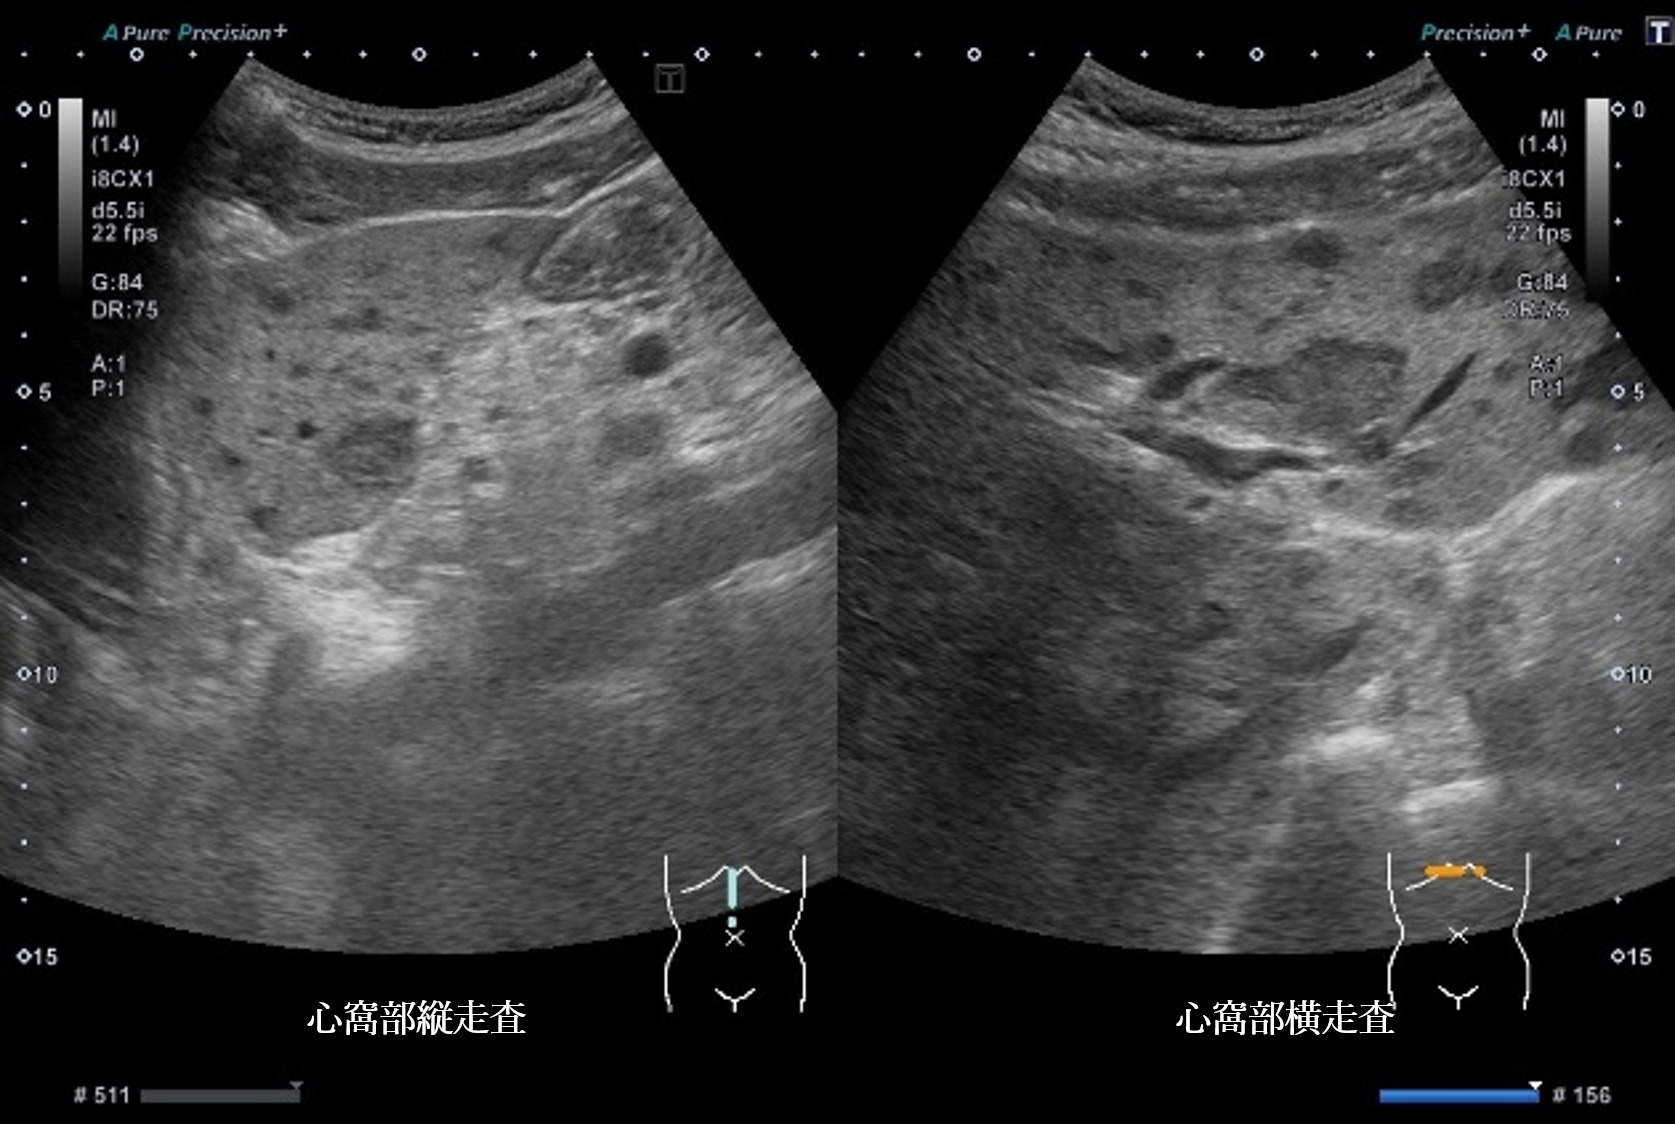

超音波所見より正しいのはどれか

① 肝全体に内部無エコーな腫瘤性病変を多数認める

② 肝全体に腫瘤性病変が多数みられ、辺縁低エコー帯を認める

③ 肝実質は粗雑不均質に観察され、明らかな腫瘤性病変は指摘できない

④ 肝全体に腫瘤性病変が多数みられ、腫瘤内部はモザイクパターンを呈する

⑤ 肝全体に腫瘤性病変が多数みられ、腫瘤辺縁にリング状高エコー像を認める

静止画および動画から超音波所見と考えられる疾患の組み合わせで正しいものはどれか

④ bull’s eye pattern ― 転移性肝腫瘍